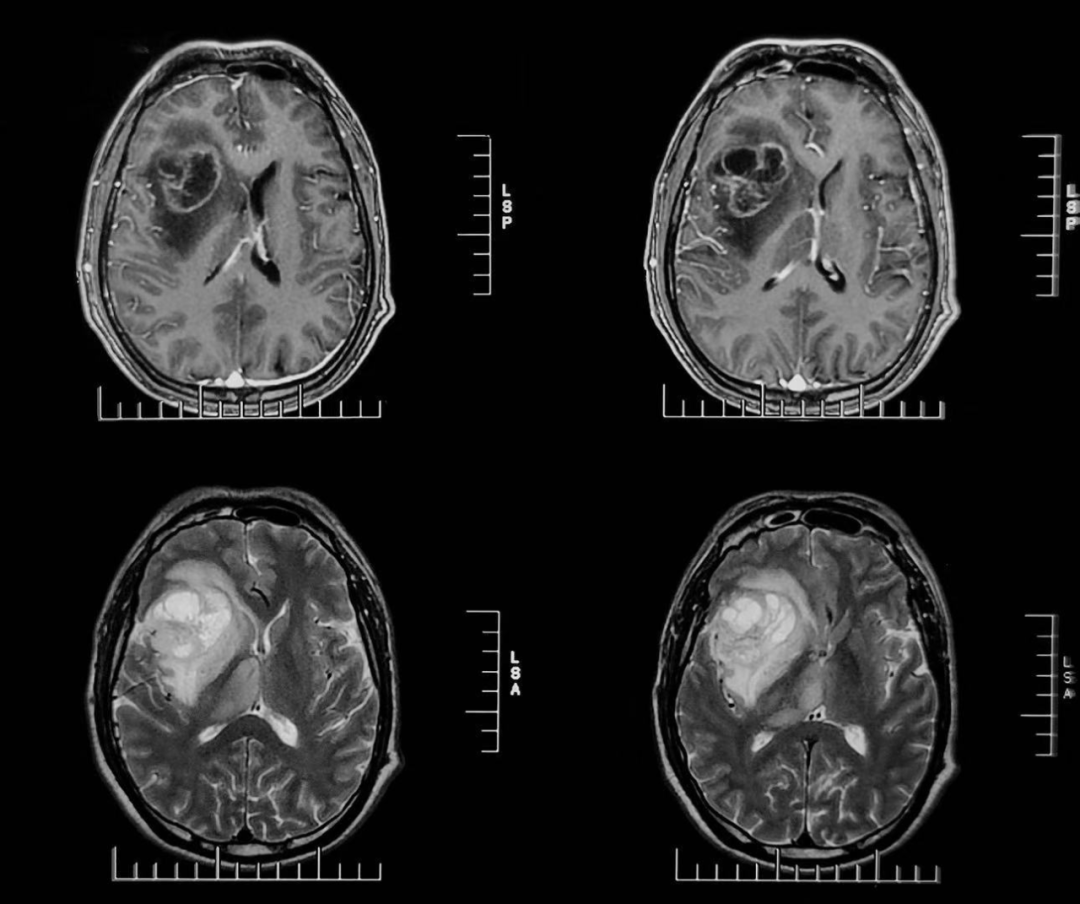

56歲的周先生(化姓)因頭痛一周入院。經(jīng)過詳細(xì)的MRS檢查,提示右側(cè)額顳島葉-放射冠-基底節(jié)區(qū)及右側(cè)丘腦異常信號,MRS顯示右側(cè)病變感興趣區(qū)局部異常譜線,符合腫瘤譜線特征。綜合考慮高級別膠質(zhì)瘤可能性大,膠質(zhì)母細(xì)胞瘤。

▲患者術(shù)前MRS影像